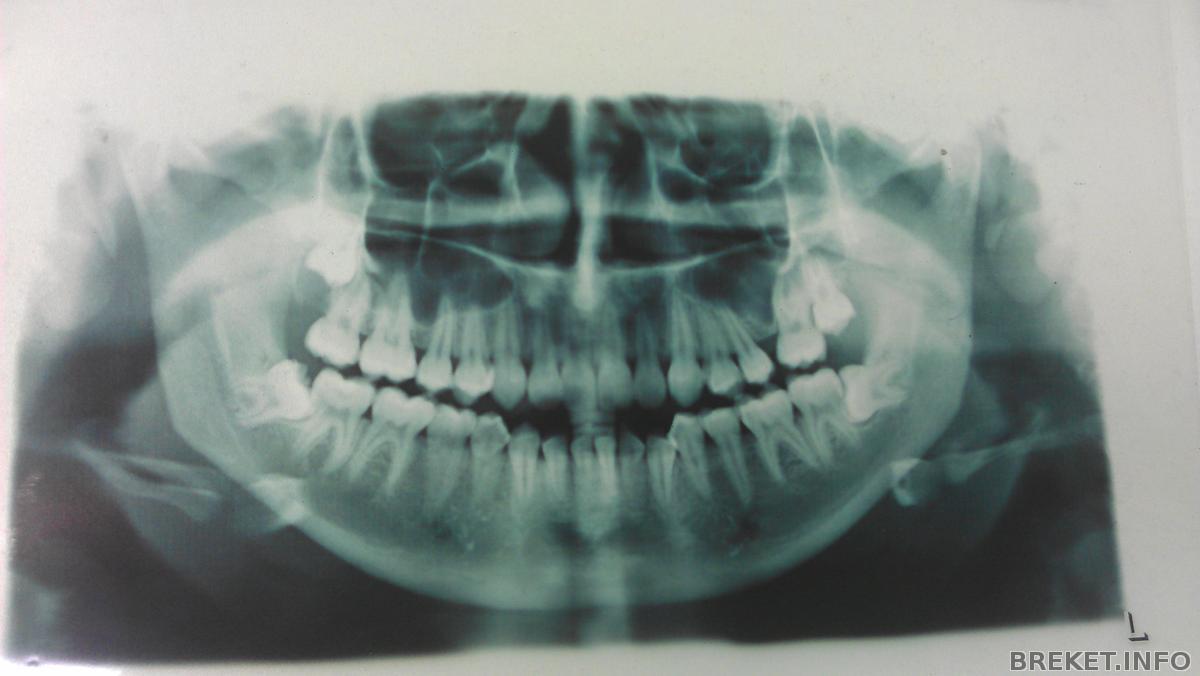

Попросила еще сфоткать старый ОПТГ (Ennelyne, Натали, специально для тебя, ты просила) и направление на новый, сегодня сделала. Думала, что все будет получше

Сегодня Panika писала про параллельность дуг..у меня ее даже а помине нет!

8-ки на НЧ нужно будет удалять, особенно левую! Она еще и с кариесом. Орта сегодня сказала в очередной раз, что она ей очень не нравится. Удалять будем планово, предварительно подготовившись.

8-ки вылезли на НЧ, но они наклонены, а на ВЧ одна вылезла (справа на снимке, она немного опустилась), в другая еще нет, но по ОПТГ видно, что она тоже опустилась немного

А восьмёрки удалять не планируется? Левая как-то совсем нехорошо лежит...